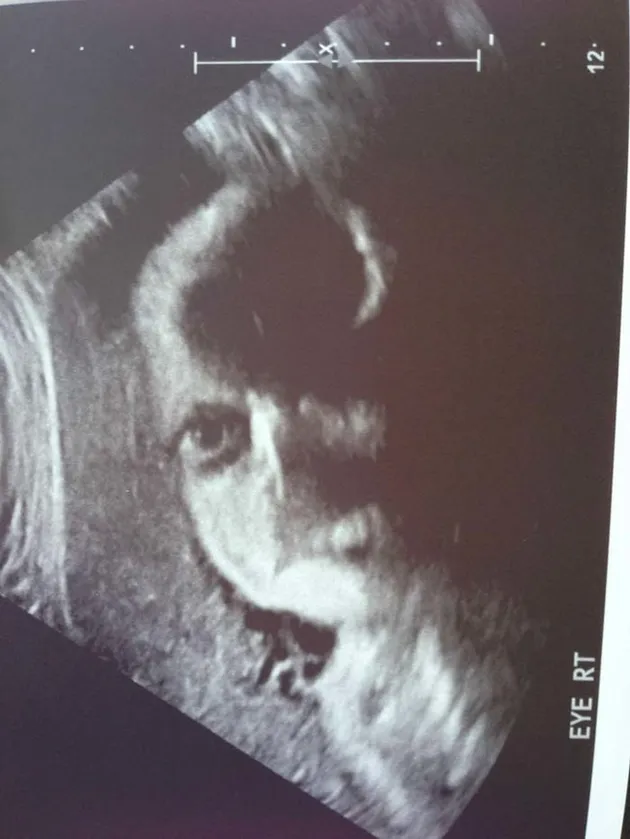

Kenali Cara Membaca Hasil USG Untuk Tahu Kondisi Bayi - Ibupedia Risiko Bayi Lahir dengan Berat Badan Rendah Bisa Dideteksi dengan USG Moms, Begini Caranya Membaca Hasil USG : Okezone Lifestyle 5 Langkah Membaca Hasil USG yang Bisa Bunda Pelajari Terekam USG, Janin Bayi Kembar Ini Saling Adu Jotos dalam Kandungan Ibunya - Semua Halaman - Grid Hot Unik! Tangan Bayi Ini Bentuk Simbol Rock N’ Roll Saat Di-USG Kesalahan Memprediksi Jenis Kelamin Saat Awal Kehamilan - kumparan.com Penjelasan di Balik Bayi Bisa Tersenyum di dalam Kandungan Viral, Rekaman USG Bayi Kembar Bertengkar dalam Rahim - Citizen6 Liputan6.com Tak Usah USG, Ini Cara Sederhana Ketahui Jenis Kelamin Bayi - Tribun Sumsel Orangtua Kaget Bukan Main saat Hasil USG Menunjukkan Bayi Melakukan Simbol Metal - Semua Halaman - Suar Ini Dia Cara Membaca Hasil USG dengan mudah - Mamapapa.id % USG Aman bagi Janin, Asalkan… Waduh, Hasil USG Tidak Bisa Dipercaya 100 Persen - Warta Kota Hiii, Hasil USG 4D Ini Tunjukkan Wajah ‘Bayi’ yang Menyeramkan Penampakan Wajah Misterius Muncul dalam Hasil USG Bayi Ini - Global Liputan6.com Hasil USG Bayi Yang Seram Ini Bisa Kasih Kamu Mimpi Buruk - ANTVKLIK Selain USG, 2 Cara Ini Terbukti Secara Ilmiah Tebak Kelamin Bayi - Berita Riau Terkini TULISAN 11. DETEKSI KELAINAN JANIN DENGAN USG – Dr. Cucuk Santoso Sp.OG Benarkah USG Membahayakan Kondisi Janin di Dalam Kandungan? | Indozone.id Cara Membaca Hasil USG yang Benar, Wajib Tahu! Gambaran Hasil Usg Kehamilan 5 Minggu Yang Perlu Diperhatikan - Hamil.co.id Viral Foto Hasil USG Perlihatkan Janin Kembar Sedang Berkelahi - Citizen6 Liputan6.com Pamer Foto USG, Bayi Nina Zatulini Sudah Mancung di Kandungan Bikin Ngeri ! ini Gambar-Gambar Hasil Ultrasonografi (USG) Terseram - Semua Halaman - Nakita Ini Dia Perbedaan USG 2D, 3D, 4D, dan 5D yang Ibu Hamil Perlu Tahu | BukaReview Manfaat USG untuk Ibu Hamil dan Janin - Ibupedia Pentingkah USG 4 Dimensi? - Mommies Daily Lihat Foto-foto Hasil USG Ini Bikin Merinding, Wajah Bayinya Menyeramkan! - Tribun Lampung Di Indonesia Juga Bisa, Sekarang Ibu Tunanetra Bisa Melihat Bayi dalam Kandungannya - Kompasiana.com Prosedur USG NT Bisa Deteksi Kelainan Janin Lebih Awal | Parenting.Dream.co.id Dokter Jelaskan Hasil USG yang Tampilkan Sosok Bayi Iblis | Republika Online USG BAYI PEREMPUAN DALAM KANDUNGAN USIA 6 BULAN - YouTube Ini Rata-Rata Berat Janin 5 Bulan - Alodokter Viral Video USG Bayi Kembar Berantem Dalam Perut Ini Bikin Gemas - Hot Liputan6.com Viral Foto USG Bayi Disebut Mirip Setan, Sang Ibu Tetap Mencintainya Berapa Kali USG Saat Hamil Harus Dilakukan? Bumil Wajib Tahu, Inilah Penyebab Bayi Sungsang dan Cara Mengatasinya Perkembangan Janin Umur 15W dalam Kandungan - Armita Consultant Gambaran USG janin perempuan usia kehamilan 29 minggu 3 hari - YouTube USG 4D Deteksi Janin Dalam Rahim - Rumah Sakit Permata Cara Membaca Hasil Foto USG Kehamilan - Cara Mengetahui Jenis Kelamin Janin Hasil USG Kehamilan 24 Minggu : “Istriku Hamil Mobil Sport!” | theAsianparent Indonesia Apakah USG Pengaruhi Perkembangan Bayi dalam Kandungan? – Islampos Ibu Panik Karena Corona, Hasil USG Janin Acungkan Dua Jari Ini Bikin Heran | merdeka.com USG foto hasil usg bayi perempuan di bali | wordsof.sandybali.com Story of My Journey: USG Kehamilan 19 Minggu 10 Foto USG bayi ini bikin merinding, mirip karakter film horor Tak Pernah Tes USG, Bayi Ini Meninggal karena Kepala Terjepit saat Lahir Usg bayi tersenyum - IbuHamil.com USG [6] : 34 Minggu 2 Hari – Jejak-jejak yang Terserak Janin Terlihat Lebih Jelas dengan MRI Dibanding USG - Health Liputan6.com Ini Dia Perbedaan USG 2D, 3D, 4D, dan 5D yang Ibu Hamil Perlu Tahu | BukaReview Cute, Bayi Dalam Kandungan Ini Acungkan Jempol Saat USG usg janin bayi 3 bulan ( 14 minggu )… Sujud kepada Allah - YouTube Hasil USG Menunjukkan Janin sedang Meniup Gelembung. Saat Sang Ibu Mengetahui Fakta itu, Dia Merasa Hancur. Lalu Bagaimana Nasib Janin itu? - Erabaru 3 Cara Membaca Hasil USG yang Benar, Biar Nggak Salah Kaprah | merdeka.com JANIN BELUM TERLIHAT SAAT USG? JANGAN KHAWATIR, MOMS! - susistory USG - Bayi Tertangkap Sedang Tepuk Tangan di Layar USG | theAsianparent Indonesia USG 34-37 MINGGU UNTUK TAU BERAT LAHIR… - dr Yudhistya SpOG | Facebook Kapan Usia Hamil Terbaik Melakukan USG? – acehimage.com Potret Malaikat Pelindung di Hasil USG - WinNetNews.com Video USG Kandungan - Lihat Seksama Apa yang Dilakukan Janin Ini di Dalam Perut - Halaman all - TribunStyle.com Cara Menghitung Berat Badan Janin Dari Hasil USG · Terbaru 2019 Ruang Media Foto USG Tampilkan Siluet Iblis Dampingi Janin : Okezone News Pahami Cara untuk Membaca Hasil USG - Tirto.ID Jenis Kelamin Bayi Beda dengan Saat USG, Ini Penjelasan Dokter Ternyata Cukup 3 Kali Melakukan USG Selama Kehamilan, Ini Penjelasannya, Moms! usg kepala bayi – Let The World Surprise You Viral Video Hasil USG Janin Bayi Kembar Seperti Sedang ‘Adu Jotos’ PERKEMBANGAN JANIN 4 MINGGU - 15 MINGGU MELALUI USG 2D / FETAL DEVELOPMENT 4 WEEKS UNTIL 15 WEEKS - YouTube Bisakah Hasil USG Salah Mendeteksi Jumlah Janin? Prosedur USG NT Bisa Deteksi Kelainan Janin Lebih Awal | Parenting.Dream.co.id USG 3D dan USG 4D, Apa Bedanya? Mana yang Lebih Baik? Janin Usia 10 Minggu, Ini Perkembangan yang Terjadi Pamer Hasil USG, Aura Kasih Bahagia Hamil Anak Perempuan Heboh Foto Dan Video USG Bayi Kembar Adu Jotos Dalam Perut – BERBAGI SEMANGAT USG 4 Dimensi Kehamilan Halaman 1 - Kompasiana.com Viral Video USG Bayi Kembar Seperti Berkelahi di Dalam Perut Ibunya - kumparan.com Kapan Kelamin Janin Bisa Di-USG? – . Bikin Ngeri ! ini Gambar-Gambar Hasil Ultrasonografi (USG) Terseram - Semua Halaman - Nakita Diary Kehamilan: USG 4D Murah Meriah – ranselriri Sering USG, Bahayakah Untuk Janin? Ukuran Kantong Janin 6 Minggu Yang Normal Dan Tidak Bermasalah - Hamil.co.id Apakah Pemeriksaan USG Berbahaya Bagi Bayi? - Dokter Indonesia Sains Buktikan Kebenaran Al-Quran Tentang Tiga Fase Bayi Dalam Kandungan | Percikan Iman Online Narsis sejak dalam Kandungan, Janin Bayi Ini Ketahuan Lagi Pose Peace saat USG | Diadona.id Masih di Dalam Kandungan, Dua Bayi Kembar Ini Saling Pukul | Keepo.me | LINE TODAY Amankah USG Bagi Janin? - DokterSehat Hamil 2 Bulan: Dari Embrio Menjadi Janin - Alodokter Ketahui Jenis Kelamin Bayi dengan Jelas Melalui USG 4D Ini Cara Deteksi Bibir Sumbing Bayi Sejak di Kandungan. Bisakah Dicegah? SERAM, FOTO-FOTO USG INI MENANGKAP SOSOK ‘BAYI HANTU’ - KapanLagi.com Langka! Hasil USG Perlihatkan Bayi Ini Tunjukkan Jari Gaya Metal USG foto hasil usg bayi perempuan di bali3 | wordsof.sandybali.com Lagi Tren Nih, Posting Hasil USG untuk Tahu Jenis Kelamin Janin Adi W Gunawan - (Kisah seorang ibu yang mampu… | Facebook Berikut Prediksi Calon Kelamin Bayi Tanpa USG | Destinasi Bandung pemeriksaan usg - Seberapa akurat pemeriksaan USG selama kehamilan? | theAsianparent Indonesia Hasil USG 2D, 3 Dimensi dan 4 Dimensi Perkembangan Janin Bayiku (24 Minggu 2 Hari) #Naya 1 - Danytrikusuma